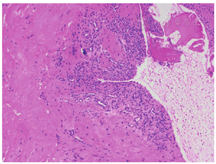

女性,66岁,因"行走不稳7年,双下肢麻木无力加重1周"于2018年6月8日入院。患者7年前无明显诱因出现行走不稳,转身困难;1周前出现双下肢麻木、无力,不能行走,双上肢无明显症状,无明显排便、排尿困难或大小便失禁,无鞍区麻木、晨僵,无关节红肿、发热畏寒等,否认既往头颈部外伤史。患者症状持续不缓解,遂于我院就诊。体检:右侧肋弓以下痛觉减退,左侧胸骨角平面以下痛触觉减退,双下肢位置觉消失,会阴部痛触觉减退不明显,两侧上肢肩外展、屈伸肘、伸腕、握拳及小指外展肌力均为Ⅴ级,两下肢屈髋、伸膝、足背伸、踇背伸及跖屈肌力Ⅱ级,双上肢肌张力无明显增高或降低,两下肢肌张力稍增高,双侧肱二头肌腱反射(++),双侧肱三头肌腱反射(++),双侧膝腱反射(+++),肛门反射(+),双侧Hoffmann征阴性,双侧Babinski征阳性。脊柱MRI检查结果示:颈椎生理曲度反弓,颈椎退行性改变,寰齿关节前间隙增宽,寰枢椎脱位,压迫相应颈髓;C7椎体向前滑移;C6~T1水平黄韧带区域占位性病变,呈T1WI低信号、T2WI高信号,考虑囊肿,椎管狭窄,相应颈髓受压、信号增高(图1)。脊柱CT平扫示:占位性病变内可见散在点状钙化。颈椎动力位X线片示:寰枢椎明显不稳。过伸位X线片示:寰枢椎脱位可复位(图2)。实验室检查:类风湿因子、抗溶血链球菌O、免疫球蛋白(IgG、IgM、IgA)、补体C3及C4、抗核抗体、抗中性粒细胞胞质抗体均呈阴性,血尿酸未见明显异常。诊断:(1)退行性寰枢椎脱位(可复性);(2)C6~T1水平椎管内硬膜外占位:黄韧带囊肿?(3)C7椎体滑移Ⅰ度;(4)不完全截瘫。因患者同时存在退行性寰枢椎脱位与C6~T1水平椎管内占位,均对颈脊髓造成明显压迫,考虑患者不完全截瘫由C6~T1水平椎管内占位所致可能性较大,但不能完全排除寰枢椎脱位影响,故于2018年6月19日在全身麻醉下行"颈后路寰枢椎脱位切开复位,椎弓根螺钉内固定术"及"颈后路C6~T1水平椎板切除及椎管减压,椎管内硬膜外占位切除,椎弓根螺钉内固定术"。术中在切除病变水平椎板后发现此处黄韧带增厚明显,可见囊肿样病变组织位于黄韧带内,被黄韧带包裹,压迫脊髓,椎管明显狭窄,病变与邻近小关节间无接触及交通。术中小心地从硬膜外剥离并完整切除病变组织及周围黄韧带,此过程中增厚的黄韧带与硬膜囊无明显粘连。体外切开病变组织见其内含凝胶样黏液,囊壁与黄韧带粘连紧密,较难分离,提示病变组织起源自黄韧带。术后复查X线片及CT可见颈椎内固定稳固,寰枢椎脱位已复位,C6~T1水平椎管减压充分(图3)。术后病理学检查示:镜下见纤维组织增生,胶原变性,部分区呈囊壁样结构,散在钙盐沉浸,并见少量软骨组织,未见滑膜层,未见异型细胞、尿酸盐沉积。病理学诊断为黄韧带囊肿(图4)。术后2周患者可在搀扶下站立;术后3个月可在搀扶下行走,但步态不稳,双下肢麻木较前有所好转;术后6个月可独自拄支具行走,但双下肢仍有麻木感,较术后3个月时无明显好转;术后9个月随访时患者可独立行走,步态仍不稳,双下肢麻木较前无进一步改善。术后未见明显并发症,患者及家属对治疗过程满意。